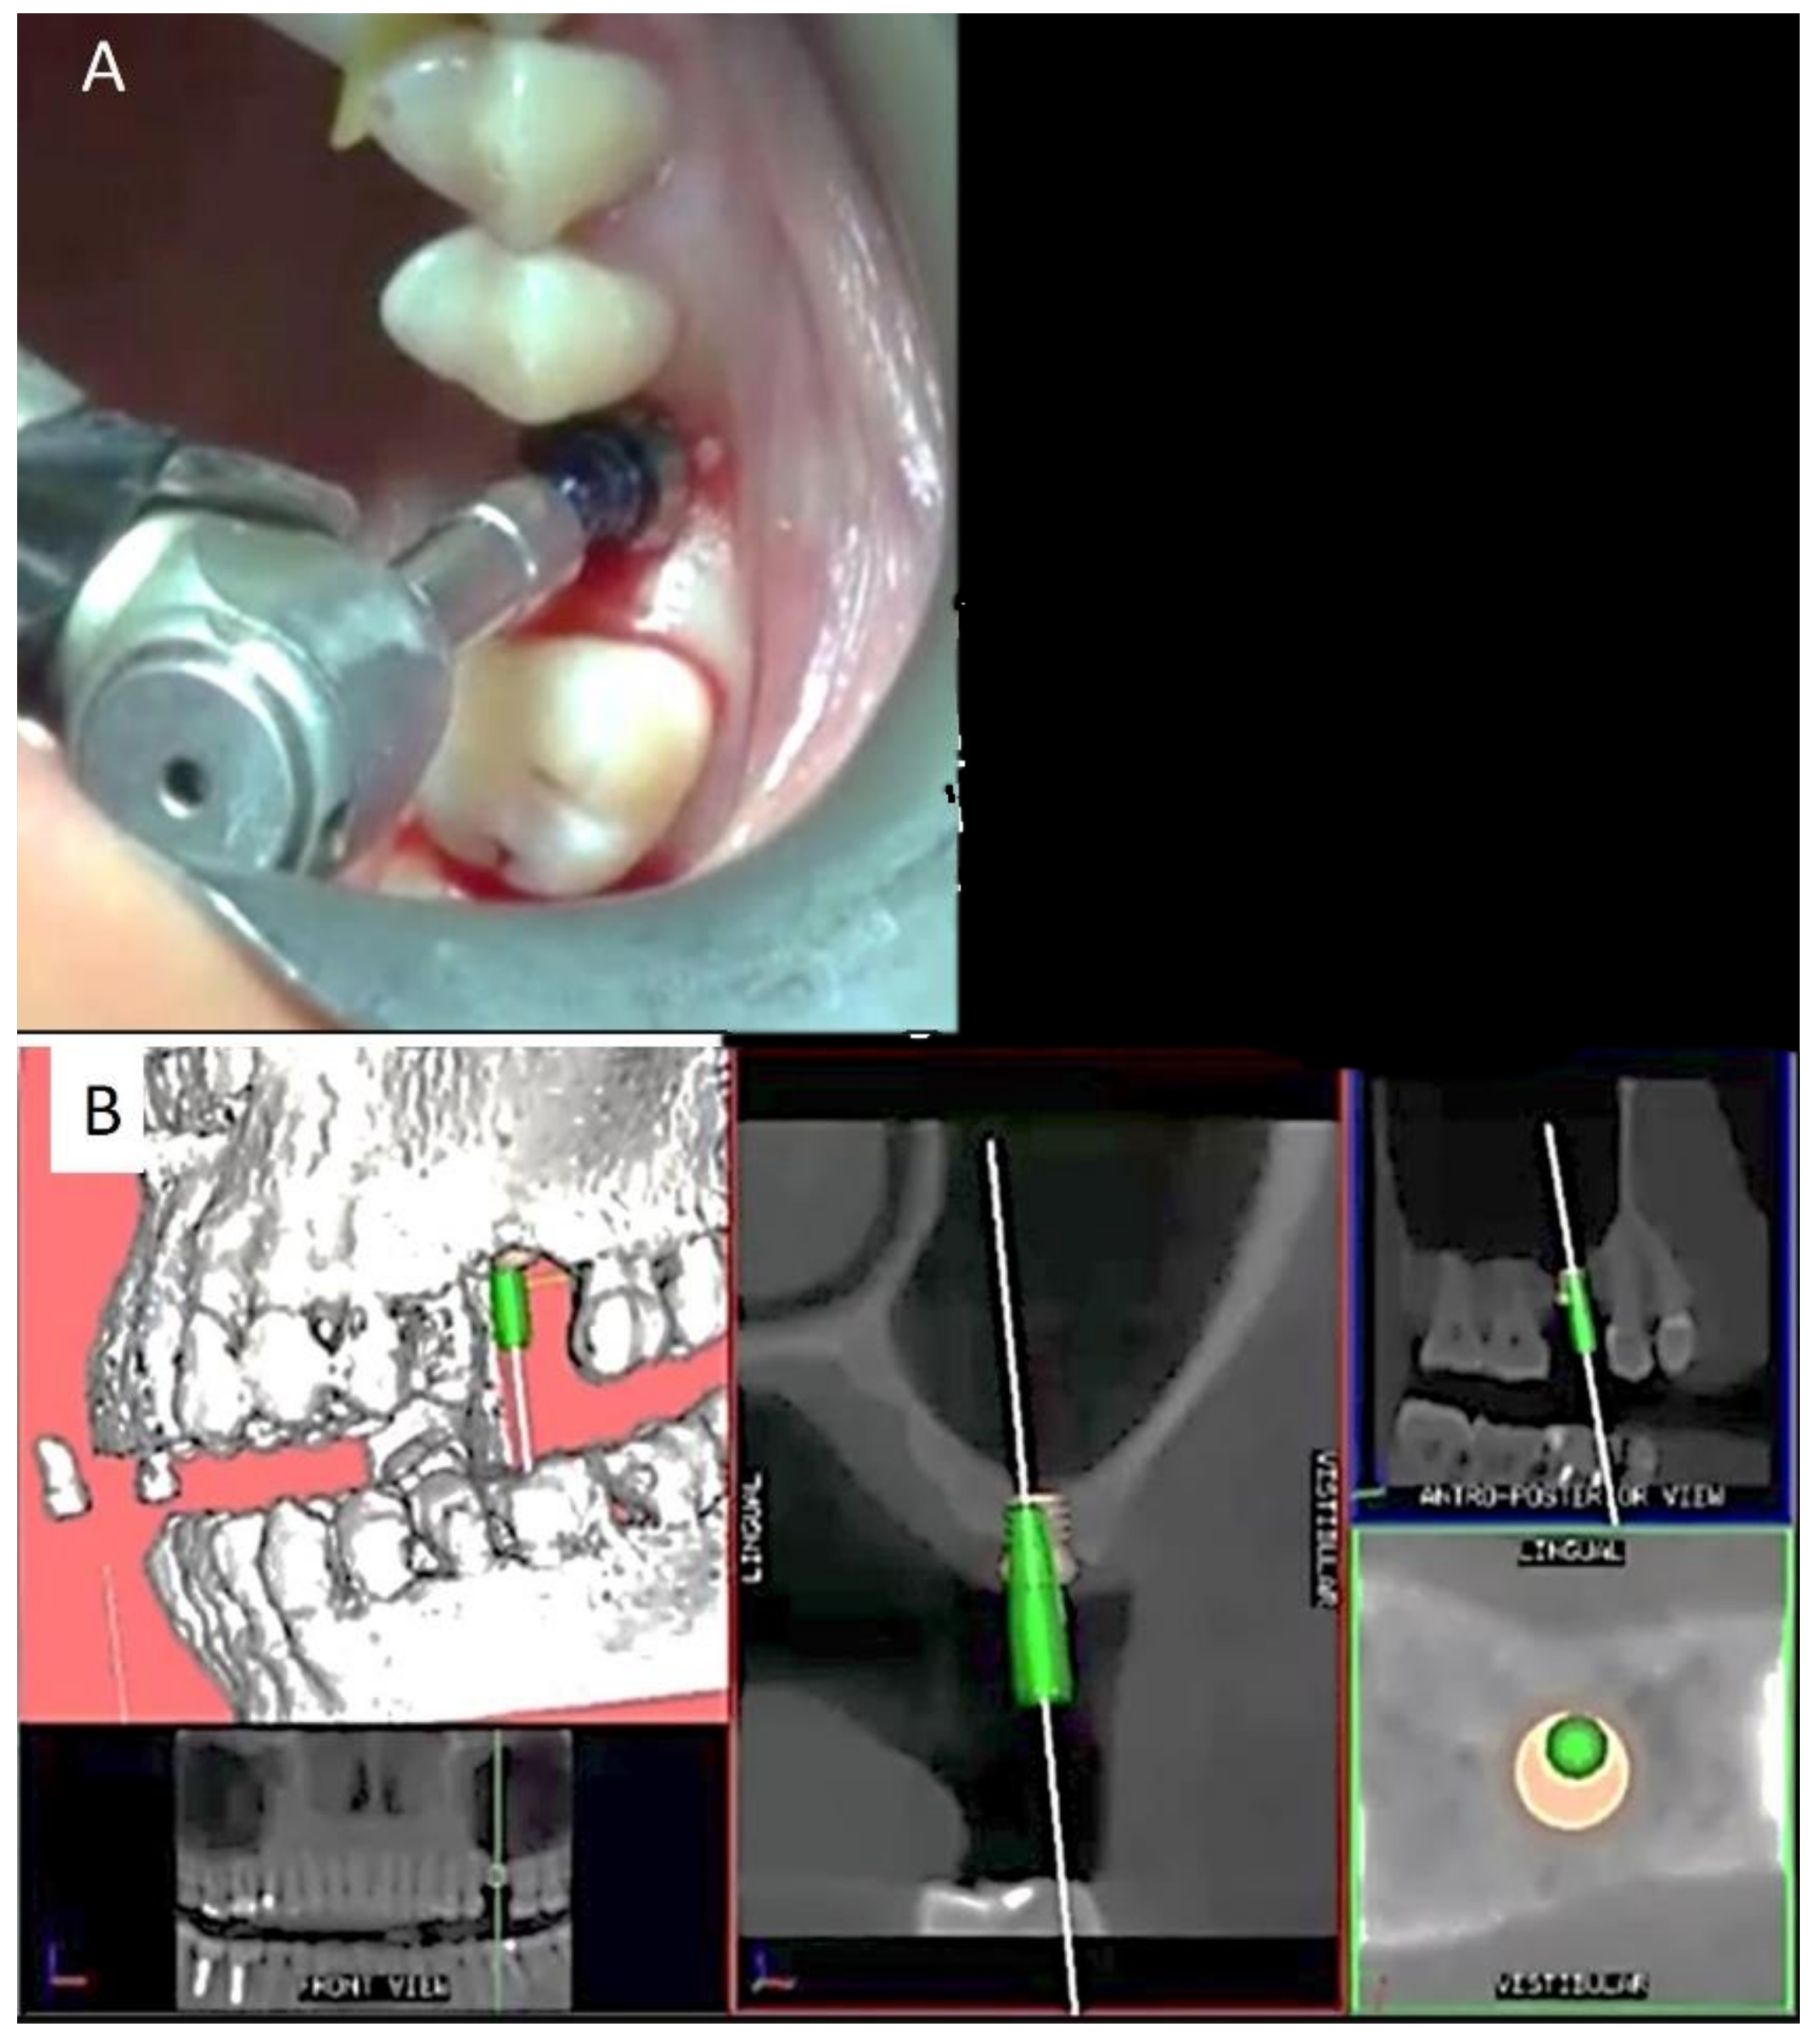

2.1. Planning

2.2. Surgical and Prosthetic Procedure